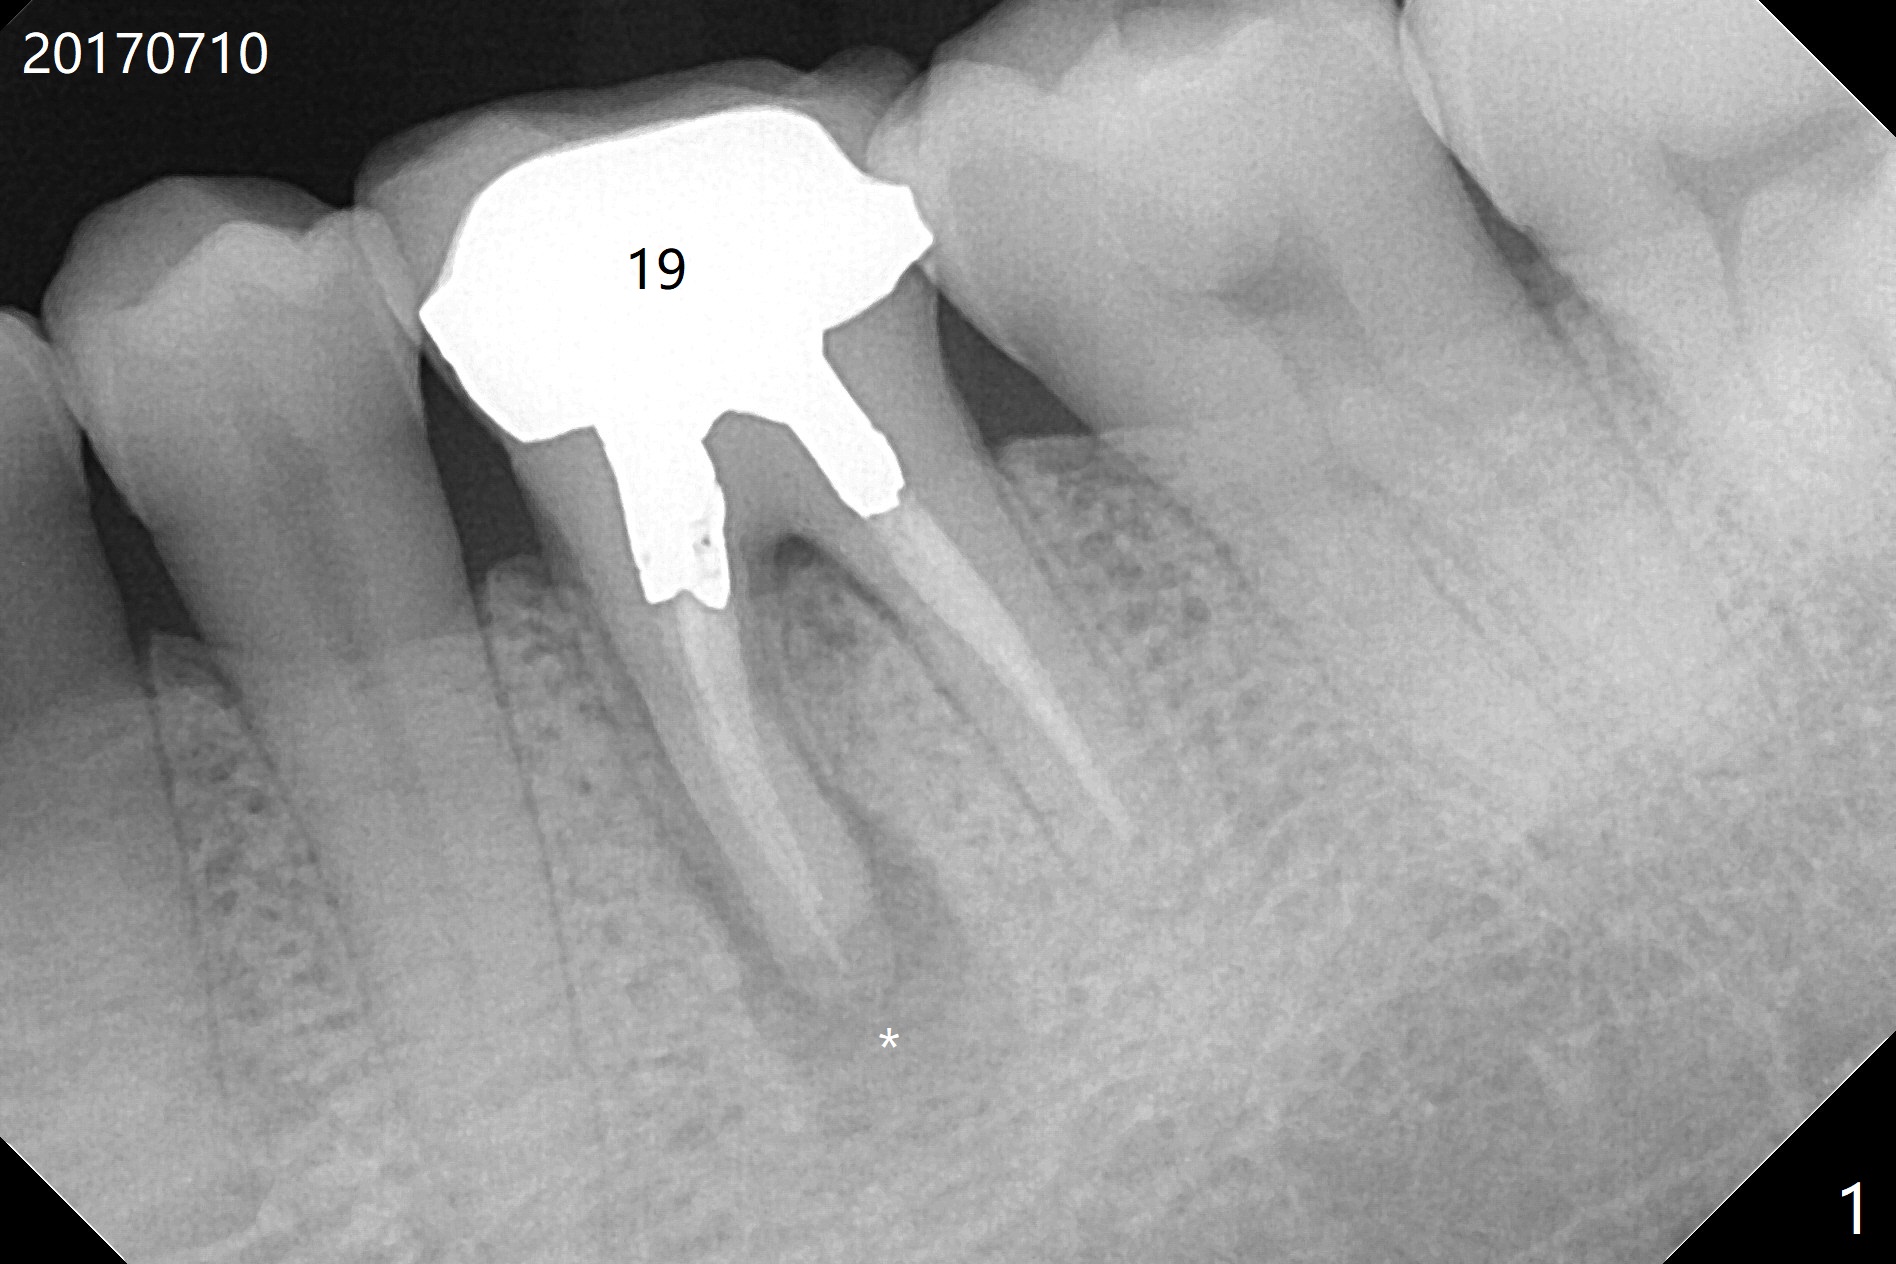

A 53-year-old man has had pain with chewing gums at #19 for 3 years (Fig.1). While a 7x17 mm implant was immediately placed at #30 six years earlier, a 5x17 mm one will be inserted at #19 as lingual as possible to reduce buccal thread exposure (Fig.2). The whole tooth will be extracted before osteotomy in the septum, since the roots in the sockets do not help free hand osteotomy unless the crown breaks off during extraction. Initial depth will be 14 mm. Use Tatum 17 mm drills. Drills are more likely deviated to the mesial socket with large PARL (Fig.1 *). Use visual acuity to correct deviation as early as possible. Pack sticky bone into the mesial bony defect for repair. Take photos of #19 and 30 for buccal recession and fistula if present. It is safe to place a 11 mm long bone level implant (Fig.3,5). It would be ideal to establish initial osteotomy as indicated by the red arrow (Fig.4).